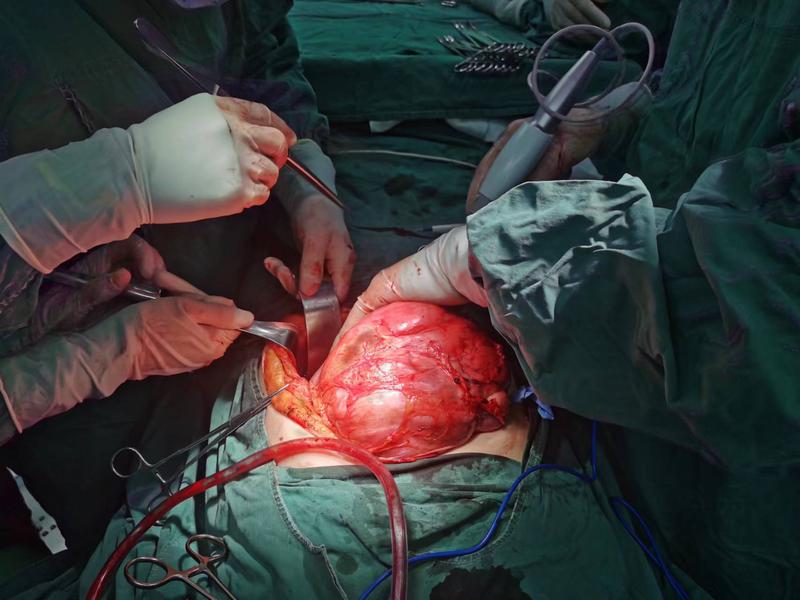

人體腹腔腹膜后有腹部龐雜的血管、神經(jīng)、淋巴系統(tǒng)和腎臟、輸尿管,左側(cè)腹腔內(nèi)有脾臟、大腸、小腸。在新生巨大的腫瘤壓迫、推擠之下,王女士腹腔臟器正常的位置和結(jié)構(gòu)已發(fā)生變化,并且王女士還患有貧血、慢性氣管炎疾病,曾有腹部手術(shù)史,以上種種均給麻醉、手術(shù)增加了難度和風(fēng)險。經(jīng)過普外科、泌尿外科、麻醉科及護(hù)理團(tuán)隊多學(xué)科溝通和嚴(yán)謹(jǐn)討論,為王女士制定了詳細(xì)的手術(shù)方案,以及術(shù)中風(fēng)險預(yù)案處置。

10月23日,普外綜合科手術(shù)團(tuán)隊為王女士實施了腹膜后巨大脂肪瘤切除術(shù),經(jīng)過2個多小時的緊張忙碌,手術(shù)團(tuán)隊完整取出一枚30*19*9cm巨大的腫瘤。術(shù)后病理檢測結(jié)果為脂肪肉瘤。目前王女士恢復(fù)順利已痊愈出院。